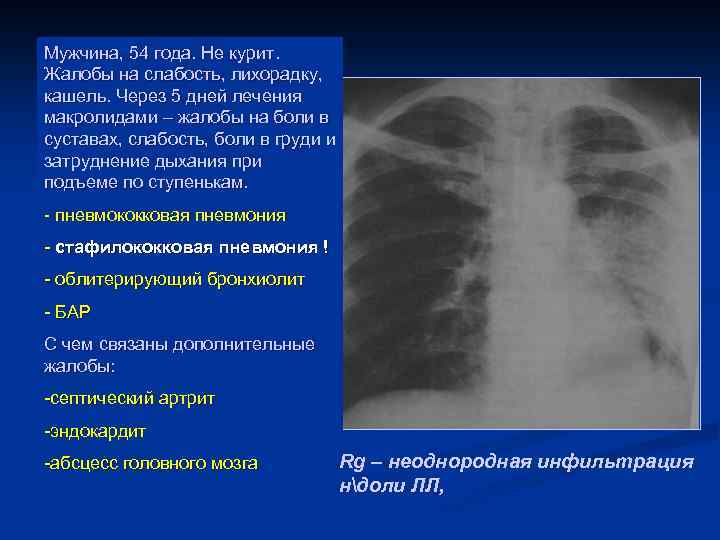

Мужчина, 54 года. Не курит. Жалобы на слабость, лихорадку, кашель. Через 5 дней лечения макролидами – жалобы на боли в суставах, слабость, боли в груди и затруднение дыхания при подъеме по ступенькам. - пневмококковая пневмония - стафилококковая пневмония ! - облитерирующий бронхиолит - БАР С чем связаны дополнительные жалобы: -септический артрит -эндокардит -абсцесс головного мозга Rg – неоднородная инфильтрация ндоли ЛЛ,